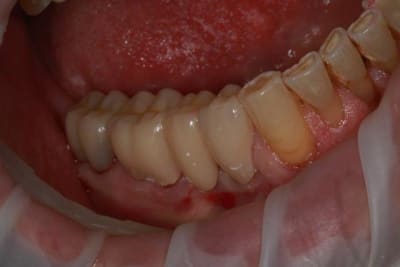

Nouveau patient, pose d'un implant il y a 2 mois....échec sans raisons particulières, douleurs et dépose.

Ce matin repose d'un nouvel implant et comme je ne veux pas prendre de risque, et que les dents adjacentes doivent être couronnées, je pose un bridge en emax press, mais scellé au ciment provisoire...

alors là pas du tout, le patient vient me voir pour des implants, donc je fais une étude du cas absence des molaires supérieures, couronnes mandibulaires très ancienne 45 racine cassée, 44 dévitalisée mais passablement déchaussée, donc avulsion de 45 et pose d'un implant avant de refaire les couronnes 46/47 et l'ensemble.

Échec implantaire, et oui ça arrive, même dans un cas paraissant simple.

Dépose gratuite bien sur et repose gratuite aussi, le bridge n'est pas facturé non plus, il le sera sous forme de 2 couronnes que cette fois ci l'implant fonctionne ce que j’espère, ou laissé en bridge si l'implant devait être retiré.